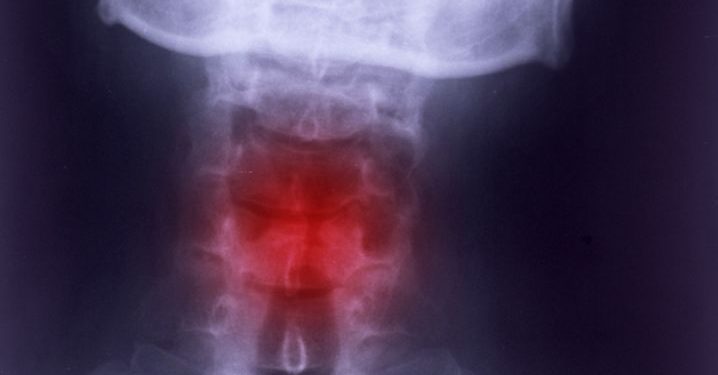

Fractures of the laryngeal skeleton are rare, occurring in one out of every 14,000 patients after trauma and are usually caused by motor vehicle crashes or personal attacks where the neck is hyperextended. They can cause airway obstruction, as seen in a case of a 53-year-old man with acute comminuted mid anterior thyroid cartilage and cricoid cartilage fractures (Figs 1(a) to 1(b)).